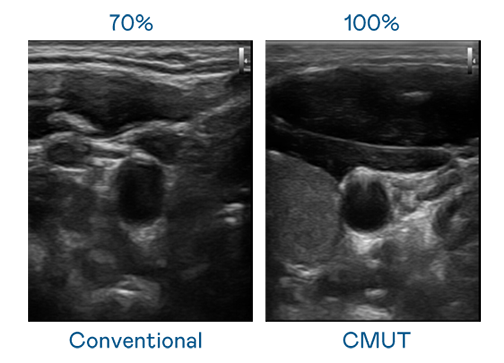

CMUT 技术是一种用电容式微机电元件来产生超音波讯号的技术。与传统 PZT 压电式技术相比,CMUT 频宽增加 30%,更宽频的超音波讯号让影像解析度大幅提升,是实现高影像品质医疗超音波扫描、促进精准医疗发展的关键技术。

超音波影像的解析度高低,首先取决于探头能发出的讯号频宽。VR彩票 CMUT 可提供高清晰的超音波讯号,提供高频宽、高灵敏度、影像纹理细节更高的超音波影像,协助医护人员缩短影像判读时间及利用精准的医疗影像进行诊断。